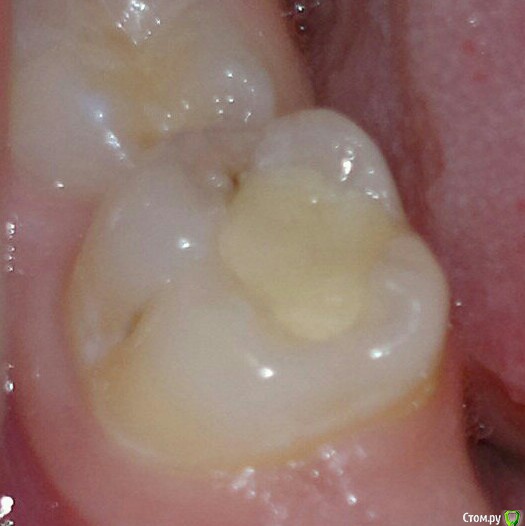

igorstom Опубликовано 24 ноября, 2019 Автор Поделиться Опубликовано 24 ноября, 2019 Ещё один пример кариеса корня зуба 3.7. Но в данном случае он неглубокий. Понятно, что световые пломбы к цементу корня не фиксируются, и 100% будет нарушение краевого прилегания, и отсюда вторичный кариес. Вопрос. Как же выйти из ситуации в данном случае, если световые пломбы в месте прилегания к корню не фиксирутся? Потом расскажу, как делаю я. Но хотелось бы услышать другие мнения. Может у кого-то есть идеи получше, чем мои решения..И да, сразу пример по поводу перелечивания каналов. Я берусь за перелечку чужого эндо, но только платно. 1 Ссылка на комментарий